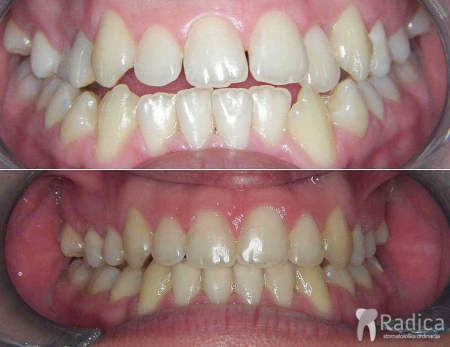

Kompresija – fiksna ortodontska terapija bez ekstrakcije (vađenja) zuba:

Kompresija – fiksna ortodontska terapija bez ekstrakcije (vađenja) zuba.

U terapiji je korišten i headgear te se napravio „striping – aproksimalna redukcija cakline “ donjih frontalnih zuba: